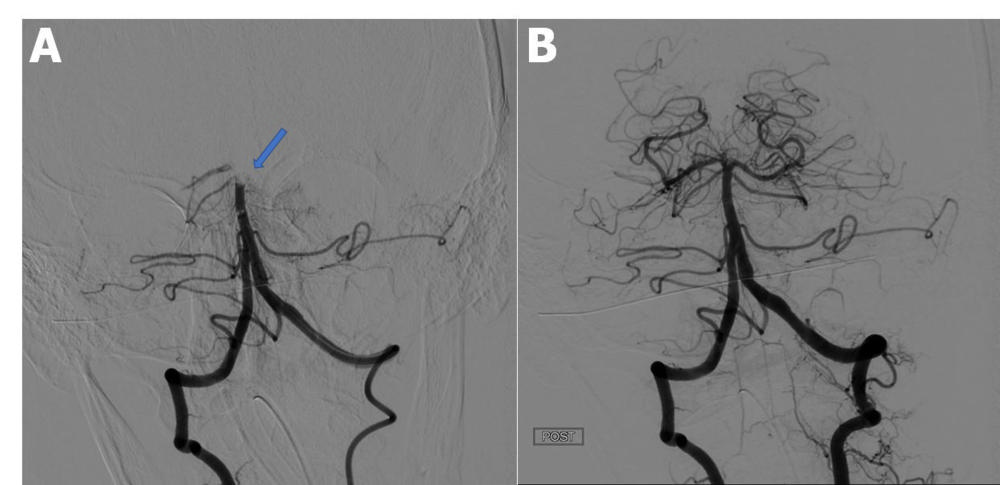

Figure 3. Catheter directed cerebral angiography. A, Pre-thrombectomy angiogram demonstrates an occluded distal basilar artery (arrow). B, Post-thrombectomy angiogram demonstrates successful restoration of the posterior circulation. (Lushina, et al.)